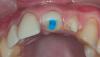

Doc Опубликовано 11 мая, 2013 Поделиться Опубликовано 11 мая, 2013 Туатти бы сделал вкв заопаченные керамикой.Он показывал такие работы. И не одну. Тут тоже показывали такие работы и не одну. Это не сильно помогает, если честно. Я это делаю регулярно, но удовольствия не испытываю особого. Вот обещанные ранее фотографии как раз подготовки под вкладку, которую заопачат керамикой. По-моему, очень ясно видно, что изменяется не только цвет дентина (это только слепой не заметит), но и цвет десны у шейки (если приглядеться чуть внимательнее). Две фотографии сделаны сразу друг за другом, с одними настройками, я не изменил ничего. А цвет десны другой! И это еще не серый КХС, а десна уже потемнела. Достаточно просто перекрыть подсветку изнутри. Когда там будет стоять металл, десна будет еще более темной и неживой. Сфотографирую с теми же настройками, когда сдавать вкладку буду. Но думаю, что и так понятно, что оптические свойства будут еще хуже. 4 Ссылка на комментарий